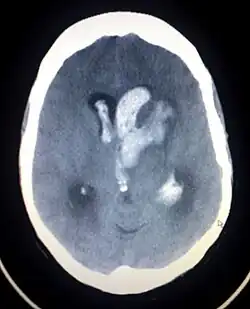

Una emorragia cerebrale è, invece, dovuta al sanguinamento all'interno del tessuto cerebrale; può essere dovuto a emorragia intraparenchimale o emorragia intraventricolare (sangue nel sistema ventricolare). La maggior parte degli ictus emorragici hanno sintomi specifici e in particolare mal di testa o un trauma cranico precedente.

Emorragia intracerebrale

Si verifica, in genere, nelle piccole arterie o arteriole del cervello ed è spesso causata dall'ipertensione,[42] da malformazioni vascolari intracraniche (compresi emangiomi cavernosi o malformazioni artero-venose), da angiopatia amiloide o infarti cerebrali in cui si è verificata una emorragia secondaria.[2] Altre cause possibili sono traumi, disturbi emorragici, angiopatia amiloide, consumo di sostanze stupefacenti (ad esempio, anfetamina o cocaina). L'ematoma formatosi si allarga fino a quando la pressione dal tessuto circostante limita la sua crescita o fino a quando non si decomprime svuotandosi nel sistema ventricolare o nel liquido cefalorachidiano. Un terzo delle emorragie intracerebrali si verifica nei ventricoli cerebrali, con un tasso di mortalità del 44% dopo 30 giorni, un valore superiore all'ictus ischemico o all'emorragia subaracnoidea (che tecnicamente può anch'essa essere classificata come un tipo di ictus[2]).